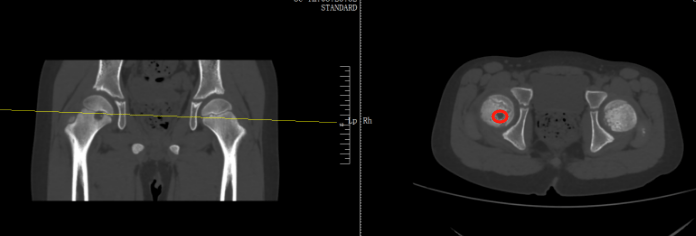

当地医生诊断为右股骨近端占位,怀疑内部可能长了肿瘤那可恩普拉托姆联vs查英特贺纳比尔 。扬扬妈妈听到医生的话心里直害怕,夫妻两人又马不停蹄带孩子来到了骨科医院进一步检查,扬扬被确诊为右股骨近端肿瘤。

好在从影像上来看,初步考虑是偏良性那可恩普拉托姆联vs查英特贺纳比尔 。在跟家长商讨过后,医生为扬扬执行了前侧入路右侧股骨头钻取刮除、取自体髂骨骨移植术,手术顺利切除病灶,并补上了股骨的“漏洞”。